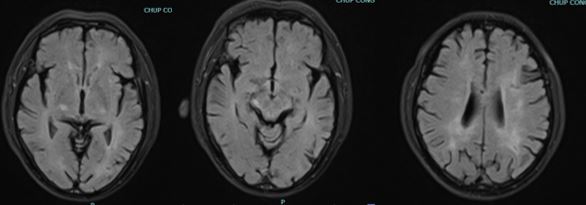

Hình CHT sọ não xung Flair.

Kết quả cộng hưởng từ sọ cho thấy tổn thương tăng tín hiệu trên xung khuyết tán tổn thương chủ yếu vùng vỏ não thùy chẩm, đỉnh 2 bên; trên xung flair tổn thương tăng tín hiệu vùng cuống não phải, dưới đồi phải, tổn thương chất trắng cạnh não thất 2 bên.